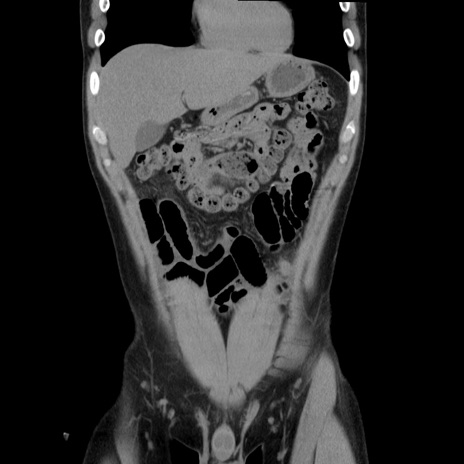

症例36(冠状断像)

【症例】20歳代 男性

【主訴】心窩部痛

【現病歴】今朝より上腹部痛あり。一旦軽快していたが再度出現したため救急要請。昨日夕に白身の魚を含む刺身を食べた。

【身体所見】BP 136/89mmHg、HR 74/min、BT 37.0℃、腹部:膨満、軟、心窩部に圧痛あり。反跳痛なし、筋性防御なし、腸雑音やや亢進あり。

【データ】WBC 17700、CRP 0.48